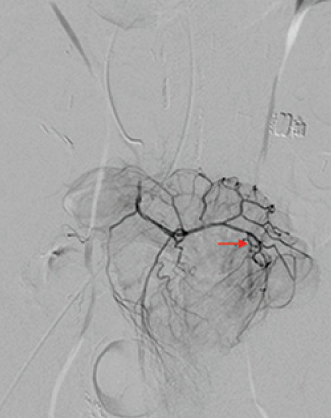

病例三 77岁女性复发性胃肠道出血,需要多次输血并入住ICU。(d)栓塞后无外渗。箭头指向栓塞部位。

激发试验药物剂量和结果![]() 、、 ![]() 本文是一篇发表在《Journal of Gastrointestinal Surgery》上的研究通讯文章,题目为“Provocative Mesenteric Angiography: Outcomes and Standardized Protocol for Management of Recurrent Lower Gastrointestinal Hemorrhage”。该研究旨在评估激发肠系膜血管造影(PMA)在复发性下消化道出血中的有效性和并发症,并探讨是否可以在多学科环境中建立一种技术操作规程。 研究方法研究团队回顾了其机构在过去12年(2008年至2020年)期间进行的下消化道出血肠系膜血管造影的数据,基于CPT代码75726筛选出符合条件的病例。进一步分析了其中的PMA病例,排除了医源性、手术性或创伤性原因引起的下消化道出血。挑衅性造影的诱导方案包括使用硝酸甘油扩张血管、肝素抗凝以及组织纤溶酶原激活剂(tPA)溶解血栓。 研究结果在12年的研究期间,共进行了36例PMA。其中16例(44%)为阳性结果,20例(56%)为阴性结果。阳性组和阴性组之间在患者人口统计学特征、既往下消化道出血史、先前住院次数、Charlson合并症指数评分或术前血红蛋白水平方面没有显著差异。所有阳性病例均接受了栓塞治疗,且无出血并发症,无再出血事件,也未出现缺血性肠病后遗症。尽管有两名患者(12.5%)在30天内因复发性出血再次入院,但这一比例显著低于在阴性研究中再出血的60%。 结论本研究是迄今为止最大的文献,表明PMA在适当选择的患者中能够成功诱发和治疗下消化道出血。此外,该程序是安全的,即使使用较高剂量的tPA,也没有发生出血或缺血性肠病并发症。研究机构采用了一种修改后的现有社会指南协议,将PMA纳入下消化道出血的管理流程。 其他信息文章还提到了一些相关的参考文献和被引用的文章,涉及早期与标准结肠镜检查、急性下消化道出血的门静脉造影预测因素和结果、隐匿性胃肠出血的挑衅性肠系膜血管造影更新等内容。这些文献提供了更多的背景信息和相关研究支持。 激发血管造影并发症 与“激发”试验直接相关的并发症